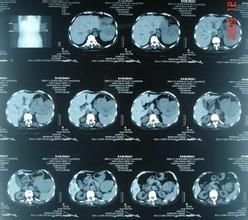

3.2CT檢查:

CT平掃發現腫瘤多呈圓形或類圓形,少數呈不規則形。良性腫瘤多小於5cm,密度均勻,邊緣銳利,極少侵犯鄰近器官,可以有鈣化表現。惡性腫瘤多大於6cm,邊界不清,與鄰近器官粘連,可呈分葉狀,密度不均勻,中央極易出現壞死、囊變和出血,腫瘤可出現高、低密度混雜,鈣化很少見。增強CT可見均勻等密度者多呈均勻中度或明顯強化,螺鏇CT尤以靜脈期顯示明顯。這種強化方式多見於低度惡性胃腸道間質腫瘤,壞死、囊變者常表現腫瘤周邊強化明顯。CT消化道三維重建對於腫瘤可協助診斷,協診GIST位置、大小、局部浸潤狀況、轉移等。